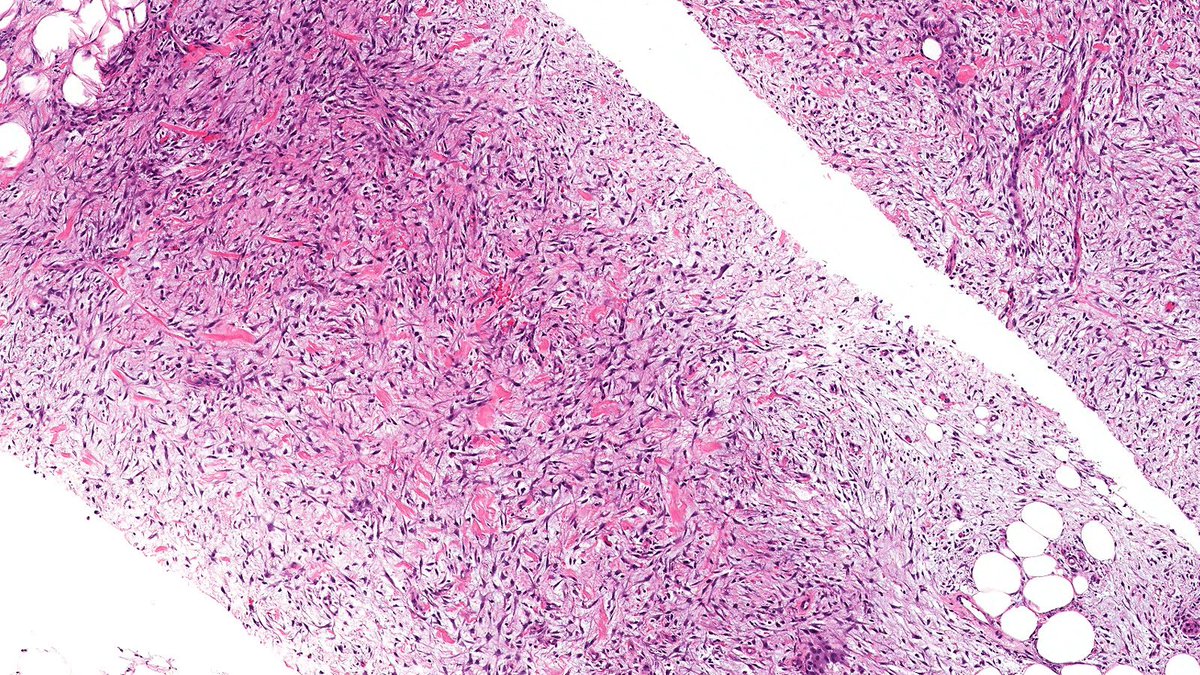

Let’s review some spindle cell breast lesions this week Case of Nodular Fasciitis (NF) 🔬 NF is a self-limited pseudosarcomatous benign neoplasm mimics malignant spindle cell lesions and harbors USP6 gene fusion. NF rarely involves the breast. #PathTwitter #PathX #breastpath

Let’s review some spindle cell breast lesions this week

Case of Nodular Fasciitis (NF) 🔬

NF is a self-limited pseudosarcomatous benign neoplasm mimics malignant spindle cell lesions and harbors USP6 gene fusion. NF rarely involves the breast.

#PathTwitter #PathX #breastpath